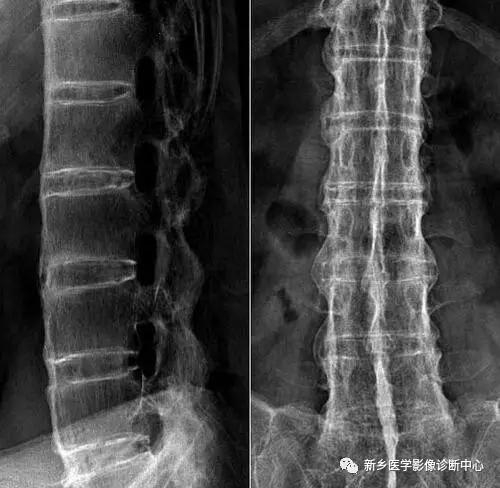

19 强直性脊柱炎

文章图片